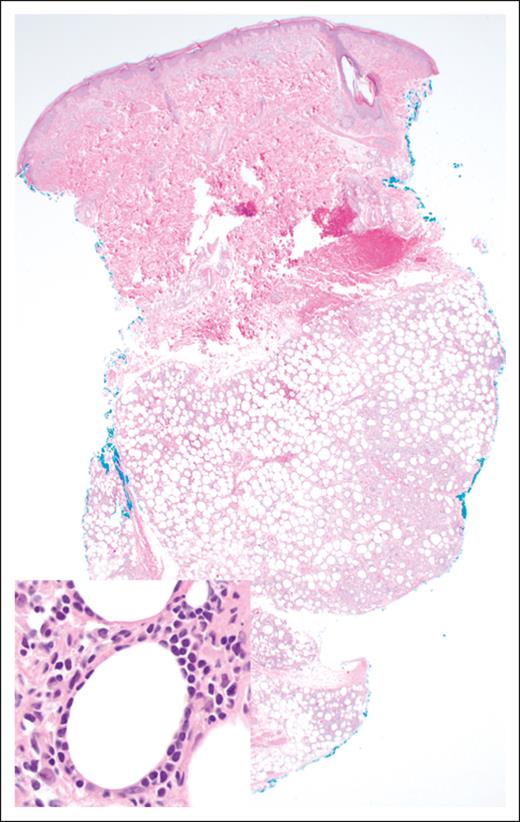

The histopathologic features of EATLs are highly variable. The neoplastic lymphocytes are generally medium to large in size and show varying degrees of pleomorphism, with some cases displaying immunoblastic or anaplastic cytomorphology.17 The tumors are frequently accompanied by a mixed inflammatory infiltrate composed of histiocytes, eosinophils, and plasma cells, which may obscure the malignant cells (Figure 1). Portions of small intestine away from the tumor mass frequently show typical histopathologic features of celiac disease.18 EATLs typically express cytoplasmic CD3, CD2, CD7, CD103, and cytotoxic markers (TIA-1, perforin, and granzyme-B) and lack CD4, CD5, and CD56 expression. Most cases do not express surface CD3 and TCR. Approximately one-third of patients are CD8+18-20 and intracellular TCRβ expression is detected in one-quarter of patients.21 CD30 expression is common in patients exhibiting anaplastic morphology, but ALK-1 is always negative,17 and the neoplastic T cells are negative for Epstein-Barr virus (EBV).

Morphologically, the malignant lymphocytes in SPTCL create a lobular panniculitis pattern with a characteristic rimming pattern around adipocytes68 (Figure 3). Most lesions feature small- to medium-sized cells, which are positive for CD8, TCR-βF1, and pan–T-cell markers CD2, CD3, CD5, and CD7 (with variable degrees of expression loss), along with cytotoxic markers TIA-1, perforin, and granzyme-B. CD30 and CD56 are negative, as is in situ hybridization for EBV encoded RNA. The proportion of proliferating cells as measured by antibodies to Ki-67 (eg, MIB-1) is high, and there is often a prominent histiocytic component, more pronounced in cases with necrosis.64,68 Although the molecular mechanisms underlying the predisposition for adipose tissue infiltration are not fully understood, the expression of CCR5 on malignant T cells and the secretion of its ligands from immunologically activated adipocytes (CCL3, CCL4, and CCL5) may contribute to the pathogenesis and clinical manifestations of SPTCL.69,70

SPTCL. The lobular subcutaneous infiltrate spares the overlying dermis and epidermis (original magnification ×20; H&E stain). Inset: the lymphoma cells display a characteristic rimming pattern around adipocytes (original magnification ×500; H&E stain).